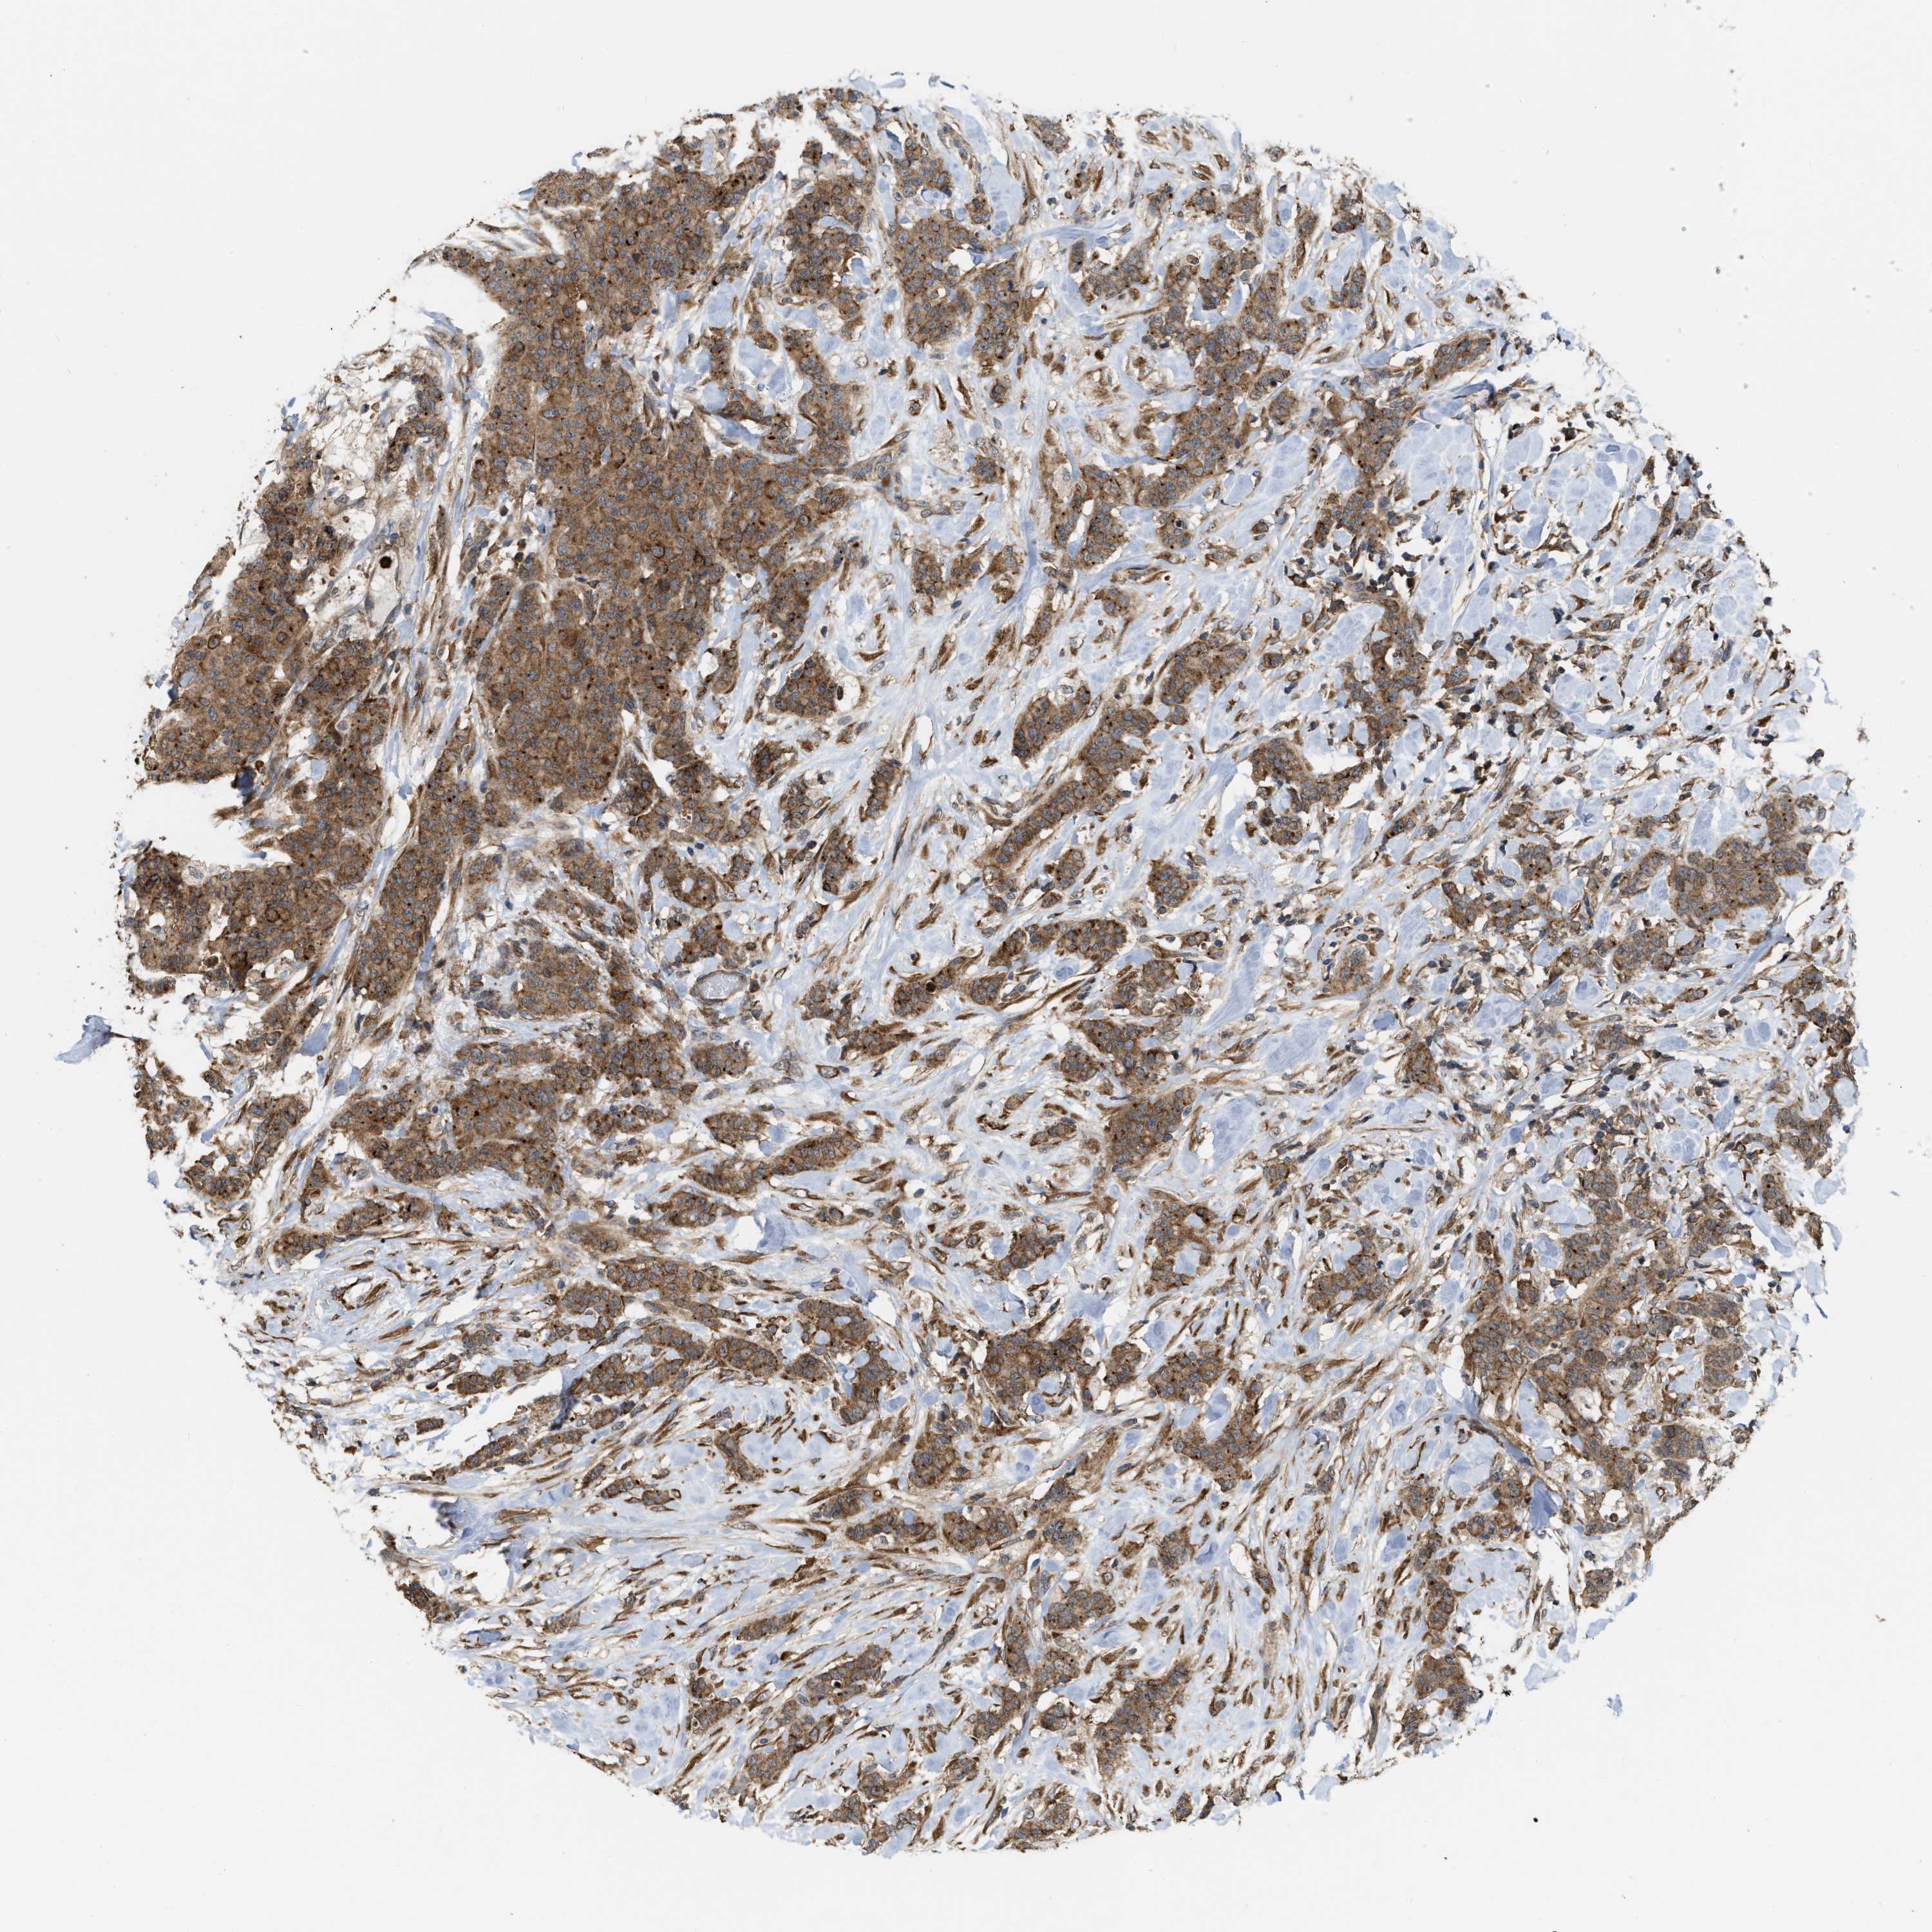

CANCER BREAST CANCER Show tissue menu

BRCA TCGA BRCA VALIDATION PROTEIN EXPRESSION